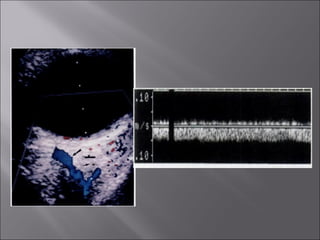

Ultrasound and CT scans provide anatomical images of the orbit, while color Doppler imaging provides visualizations of vascular structures and blood flow within lesions. These imaging techniques are used to evaluate a variety of orbital conditions involving blood vessels, infections, tumors, congenital issues, trauma, and more, and can help identify vascular disorders, thrombosis, treatment responses, and dynamic changes in benign tumors over time.